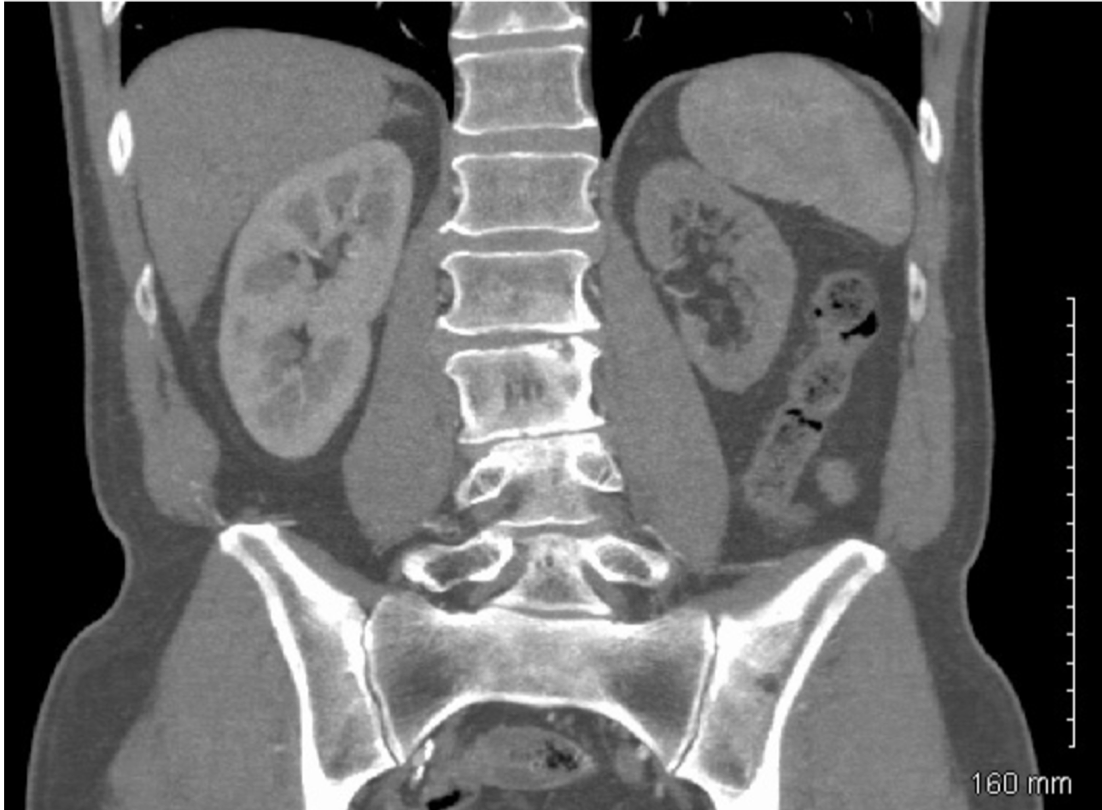

A 65 yo patient comes in complaining of abdominal pain after eating who has a BP of 175/110.

CT scan of the abdomen reveals the following:

What condition is this patient most likely suffering from?

Renal artery stenosis